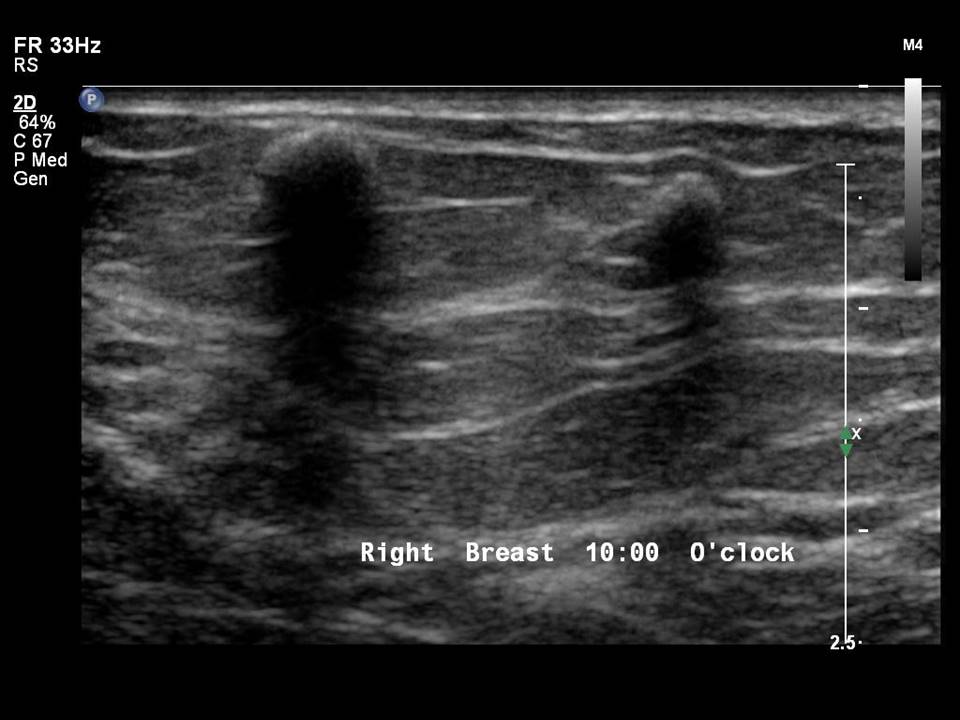

Breast Ultrasound cancer 1 YouTube What Does Shadowing Mean On Breast Ultrasound When silicone leaks out of the implant it will cause a. 30% multiple projections from the nodule within or around ducts. This loss is displayed in the image as. Sometimes this lobulation can give the impression of a lump in the breast (figure). As ultrasonic beams propagate through tissues, there is a loss of energy by absorption, reflection and scattering.. What Does Shadowing Mean On Breast Ultrasound.

Right breast ultrasound demonstrates an irregular shaped, hypoechoic What Does Shadowing Mean On Breast Ultrasound When silicone leaks out of the implant it will cause a. As ultrasonic beams propagate through tissues, there is a loss of energy by absorption, reflection and scattering. 30% multiple projections from the nodule within or around ducts. Acoustic shadowing occurs when an ultrasound beam encounters a highly reflective or dense structure within the body. Collections or silicone leakage **.. What Does Shadowing Mean On Breast Ultrasound.